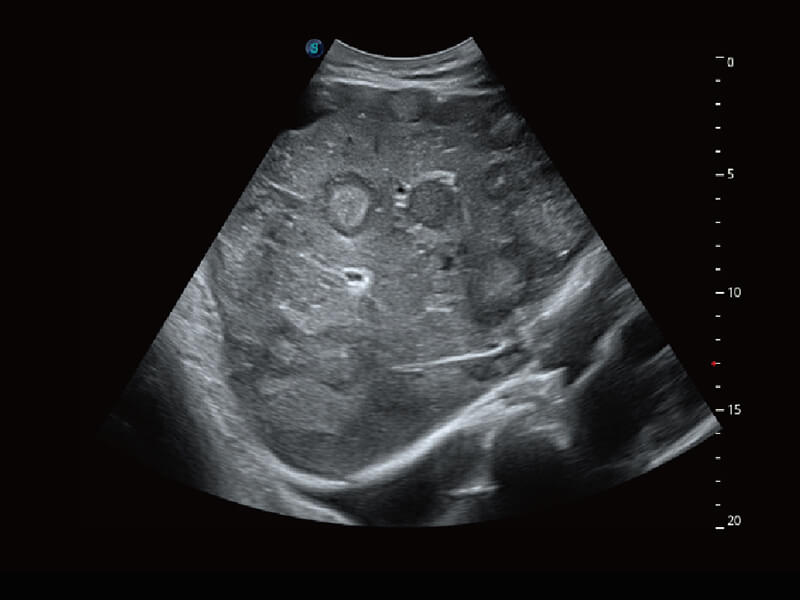

成像功能

性能优异的硬件架构,极大提升超声系统的运行效率和数据处理能力。相比以往超声成像系统,Wis+平台为您带来极快的响应速度和成像帧频,提升检查流畅度。

S60探头工艺,从前端信号处理每一个环节采集无损声学数据,真实还原组织原貌,再现解剖细节。